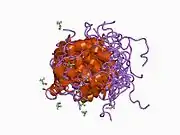

Band 3 anion transport protein, also known as anion exchanger 1 (AE1) or band 3 or solute carrier family 4 member 1 (SLC4A1), is a protein that is encoded by the SLC4A1 gene in humans.

Band 3 anion transport protein is a phylogenetically-preserved transport protein responsible for mediating the exchange of chloride (Cl−) with bicarbonate (HCO3−) across plasma membranes. Functionally similar members of the AE clade are AE2 and AE3.[5]

- Electroneutral chloride and bicarbonate exchange across the plasma membrane on a one-for-one basis. This is crucial for CO2 uptake by the red blood cell and conversion (by hydration catalysed by carbonic anhydrase) into a proton and a bicarbonate ion. The bicarbonate is then excreted (in exchange for a chloride) from the cell by band 3.

- Physical linkage of the plasma membrane to the underlying membrane skeleton (via binding with ankyrin and protein 4.2). This appears to be to prevent membrane surface loss, rather than having to do with membrane skeleton assembly.

The erythrocyte isoform of AE1, known as eAE1, is composed of 911 amino acids. eAE1 is an important structural component of the erythrocyte cell membrane, making up to 25% of the cell membrane surface. Each red cell contains approximately one million copies of eAE1.